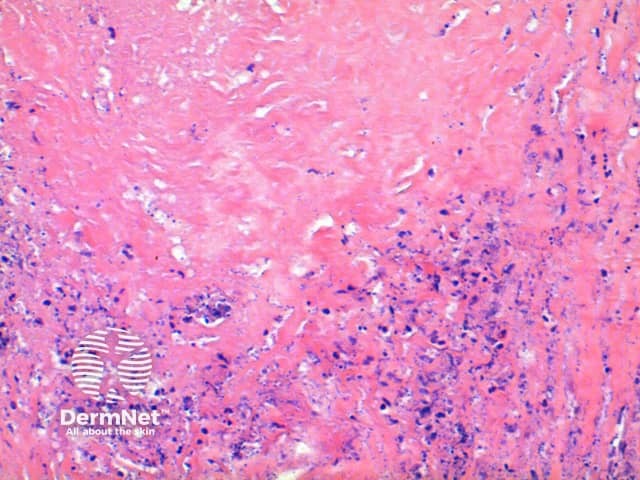

The scanning view of the histology of granuloma annulare shows a granulomatous inflammatory pattern situated within the superficial and mid dermis.

Figure 1